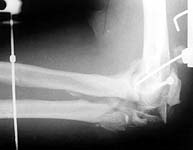

A manual labourer admitted to our unit couple of days afer a train accident with the open injury.

The wound is small, debrided in the initial hospital and shows no signs of infection at the moment.

As a first step an external fixator applied yesterday, with percutaneous screw fixation of the lateral epicondyle.

If no signs of infection he is ready for further procedures within few days. What plan is optimal for the case? Attempt of open reduction of the "mosaic" and plating? Early functional treatment without open procedures? Reinsertion of olecranon and small fragment removal? Total elbow replacement?